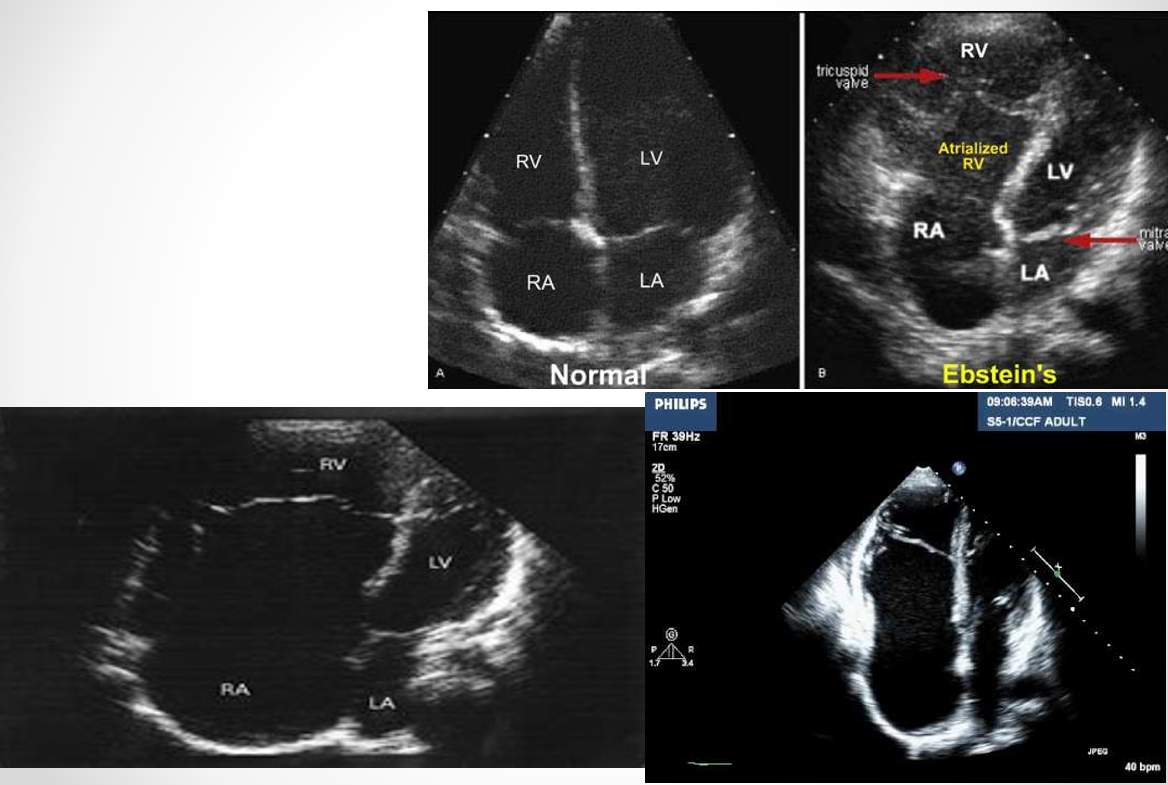

what is the ebstein anomaly? (DONT FOCUS ON)

apical displacement of one or more leaflets

insertion of tricuspid leaflet downward into RV (greater than 10mm from mitral valve leaflets)